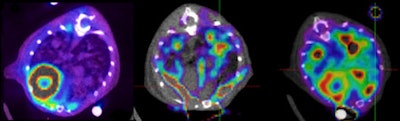

L-type amino acid transporter 2 (LAT2) transgenic mice PET/CT scan shows pulmonary adenocarcinoma. Left: F-18 FDG, middle: methionine-11C, right: choline-11C. All images courtesy of Drs. Fanti and Nanni.Is sufficient funding currently available for molecular imaging research in Europe?